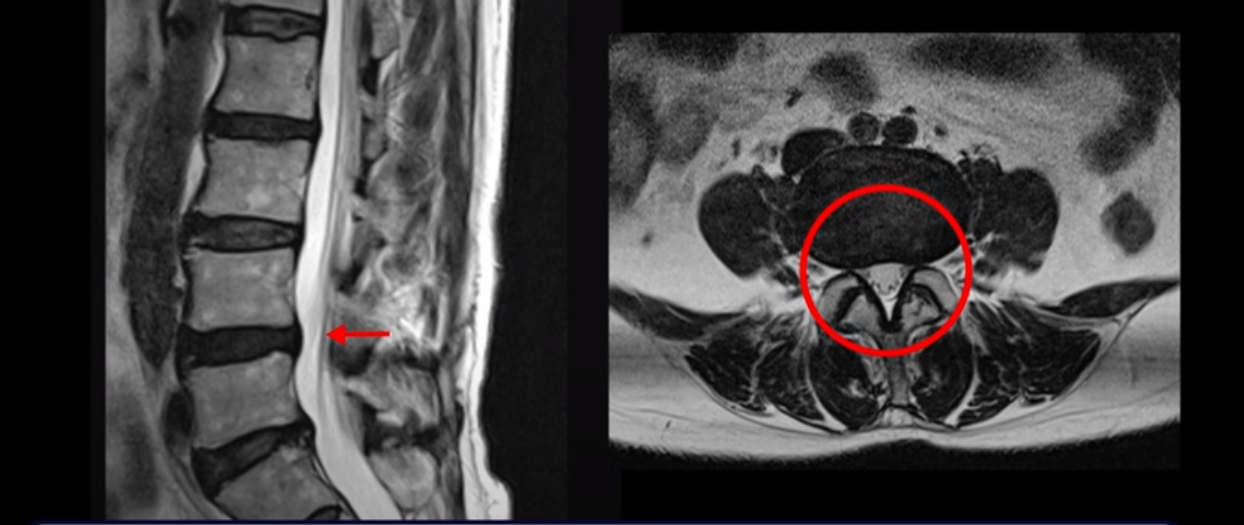

이 환자분 MRI 보면서 설명 드린 후 왜 이런 환자는 신경주사가 효과가 없는지 왜 근육재활치료를 꼭 받아야 하는지, 근육재활치료로 어떻게 좋아질 수 있는지 설명 드리도록 하겠습니다. 이분MRI를 보면 허리 여러 마디 퇴행이 진행되어 있고 디스크와 협착도 있지만 아주 심해 보이지는 않습니다.

이분 다리는 양쪽이 다 아픈데 양쪽 추공간이 좁아져 있긴 하지만 여전히 하얀 지방이 많이 보이는 상태로 심하게 좁아 보이지는 않습니다.

척추관이 가장 좁아진 4번 5번을 보면 중심성 협착이 있지만 많이 심하지는 않습니다

그런데 저희가 협착증 발병과 치료에 근육이 너무나도 중요하다고 하는 이유는 이렇게 신경 구멍이 심하게 좁아지지 않은 환자도 근육 상태가 안 좋아지면 얼마든지 신경학적 방사통이 생길 수 있기 때문입니다. 이분은 몇 개월 전 아기를 보면서 허리를 무리하게 쓴 후 다리 증상이 시작되었고 그 뒤에 해외 여행 다녀온 이후 증상이 급격히 악화됩니다. 60세 이후 노화와 퇴행으로 신경 구멍들이 조금씩 좁아지고 근육은 줄어들고 약해진 상태에서 무리한 일이나 운동으로 근육의 문제가 심해지면 근육이 허리를 잘 지탱하지 못하니까 신경 눌림 증상이 얼마든지 발생할 수 있습니다. 그런데 심해 보이지 않는 협착도 이 환자분처럼 일단 방사통이 생기고 신경주사가 듣지 않으면 수술하자는 얘기를 듣게 됩니다.